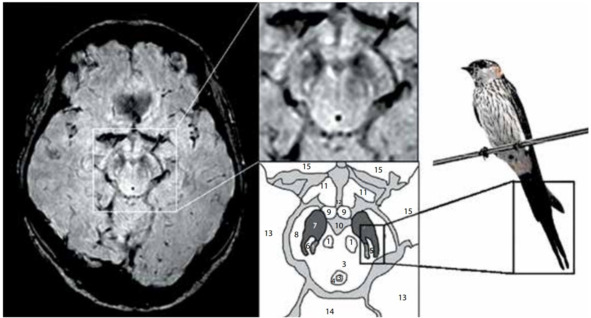

По результатам Stefan T. Schwarz при выполнении МРТ головного мозга на аппаратах повышенной мощности (7 Тесла) и разрешающей способности удается обнаружить структурные изменения тканей мозга в центральной зоне substantia nigra, характерные для людей с БП. В ходе наблюдений было выявлено, что у здоровых людей эта область напоминает изображение хвоста ласточки (рис. 15). У пациентов с БП характерное разделение черной субстанции на две доли «ласточкиного хвоста» пропадает. Для проверки своего метода ученые провели 114 сканирований головного мозга с высоким разрешением. В 94% случаев им удалось поставить точный диагноз. Дальнейшие исследования показали, что «ласточкин хвост» (и его отсутствие) можно разглядеть и на аппаратах мощностью 3 Тесла.

Рис. 15. МРТ (3 Тл, SWI) здорового человека, аксиальный срез на уровне нигросомы 1 с увеличением среднего мозга (справа, сверху) и схематическим изображением соответствующих анатомических структур (справа, снизу): 1 – красное ядро, 2 – покрышка среднего мозга, 3 – водопровод, 4 – периводопроводное серое вещество, 5 – медиальная петля, 6 – нигросома 1, 7 – черное вещество, 8 – ножки мозга, 9 – сосцевидное тело, 10 – интерпедикулярная ямка, 11 – зрительная лучистость, 12 – третий желудочек, 13 – височная доля, 14 – мозжечок, 15 – лобная доля [Schwarz S.T et al., 2014].